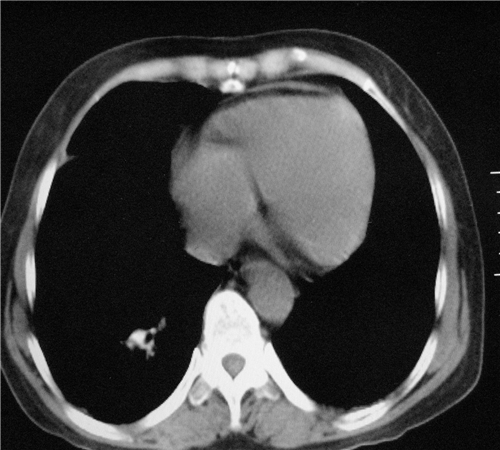

标题: CT26849:女67岁反复胸痛两天余,临床考虑夹层。 [打印本页]

标题: CT26849:女67岁反复胸痛两天余,临床考虑夹层。

右肺感染,未见夹层。

未见夹层

既然考虑夹层,建议强化!另:右下肺感染!

1)右肺感染性病变。2)建议行ct增强扫描或mri检查排除主动脉夹层。

双下肺感染,右侧显著。有无夹层,增强扫描后再诊断。

1. 感染性病变,2.未见夹层,3.食道未见异常。

平扫未见确切夹层征,建议必要时增强扫描或mri检查。